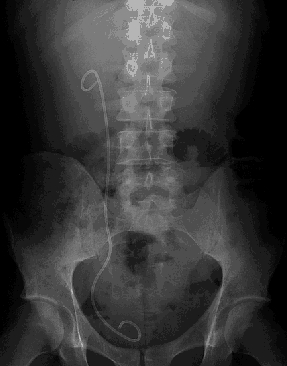

Pour ma santé, ça va, on m'a retiré ma sonde double-J (gif 23Ko)